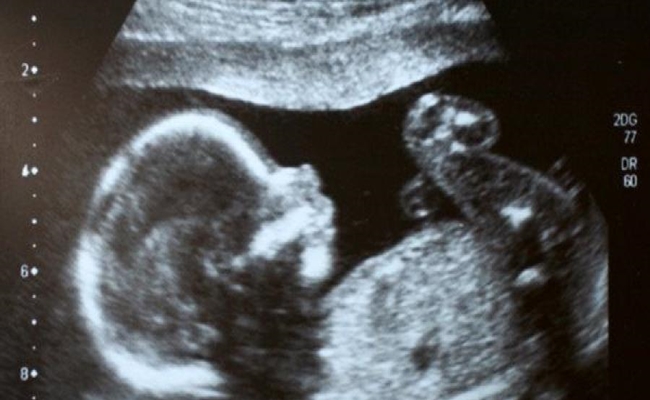

إجراء أول عملية جراحية في العالم لدماغ جنين داخل رحم أمه

نجح أطباء أميركيون في إجراء عملية جراحية لدماغ جنين في رحم أمه، لعلاج حالة طبية نادرة، هي الأولى على مستوى العالم.

وباستخدام الموجات فوق الصوتية، تمكن الأطباء من علاج التشوه الذي يسبب تدفقا للدم بسرعة كبيرة عبر جزء من الدماغ، وهي أول حالة مماثلة تعالج بهذه الطريقة.

وأجرى أورباخ وزملاؤه العملية لجنين في الأسبوع الـ34 من الحمل، واستخدموا الموجات فوق الصوتية لإرشادهم في أثناء العملية. وولدت الطفلة بعد يومين، لأن العملية تؤدي إلى تمزق الأغشية في الرحم، فيولد الطفل قبل الأوان.